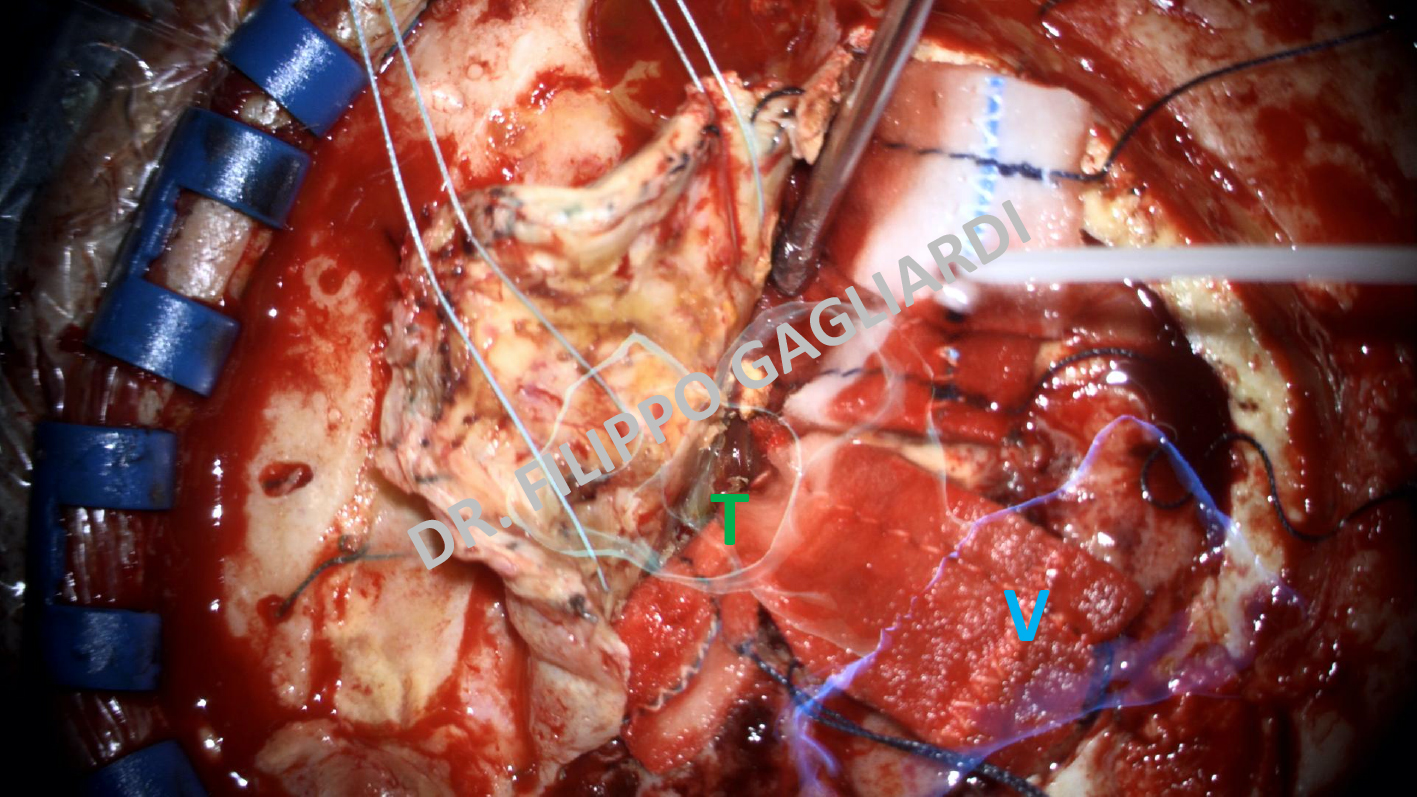

Realtà virtuale aumentata